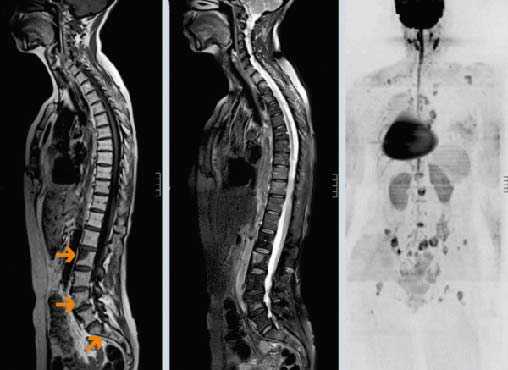

Патологические переломы возникают при разрушении более 50% кортикального слоя. Чаще всего выявляются в позвонках, второе место по распространенности занимают переломы бедренной кости, обычно – в области шейки или диафиза. Отличительной особенностью патологических переломов позвоночника при метастазах в кости является множественность поражения (одновременно выявляется нарушение целостности нескольких позвонков). Как правило, страдает грудной или поясничный отдел. Повреждения могут сопровождаться компрессией нервных корешков или спинного мозга.

Компрессия спинного мозга

Компрессия спинного мозга выявляется у 1-5% пациентов с метастатическими поражениями позвоночника. В 70% случаев причиной нарушений становятся метастазы в грудные позвонки, в 20% - в поясничные и крестцовые позвонки, в 10% случаев – в шейные позвонки. При метастазах в кости могут выявляться как острые (при сдавлении костным фрагментом), так и постепенно прогрессирующие (при сдавлении растущей опухолью) расстройства. При сдавлении растущим новообразованием пациентов с метастазами в кости беспокоят нарастающие боли. Развивается мышечная слабость, выявляются нарушения чувствительности. На заключительной стадии возникают парезы, параличи и нарушения функции тазовых органов.

При сдавлении фрагментом кости клиническая картина компрессии спинного мозга развивается внезапно. На начальных стадиях оба вида компрессии обратимы (полностью или частично). При отсутствии своевременной медицинской помощи в течение нескольких часов или дней паралич становится необратимым. Своевременное адекватное лечение позволяет уменьшить выраженность симптомов, однако восстановление способности к самостоятельному передвижению отмечается всего у 10% больных с уже развившимся параличом.

Диагноз устанавливается на основании анамнеза (данных о наличии первичного злокачественного новообразования), клинической картины и результатов дополнительных исследований. Отсутствие информации об уже диагностированном онкологическом заболевании не является основанием для исключения метастазов в кости, поскольку первичная опухоль может протекать бессимптомно. При наличии неврологических нарушений проводят неврологический осмотр. На начальном этапе обследования выполняют сцинтиграфию. Затем больных направляют на рентгенографию, КТ или МРТ кости для уточнения характера и распространенности поражения. Для выявления гиперкальциемии назначают биохимический анализ крови.

О наличии онкологического заболевания свидетельствует положительный анализ крови на онкомаркеры. На начальном этапе диагностики больным с подозрением на метастазы в позвоночник назначают рентгенографию позвоночника. На ранних стадиях метастазирования рентгенологические признаки поражения позвонков могут отсутствовать, поэтому при отрицательном результате исследования пациентов с подозрением на метастазы в позвоночник направляют на сцинтиграфию, КТ и МРТ позвоночника. Для выявления первичной неоплазии и вторичных очагов проводят УЗИ органов брюшной полости, рентгенографию органов грудной клетки, маммографию и другие диагностические процедуры. Дифференциальную диагностику метастазов в позвоночник осуществляют с сосудистыми поражениями, последствиями воспалительных заболеваний, вторичной демиелинизацией и первичными неоплазиями позвоночного столба.